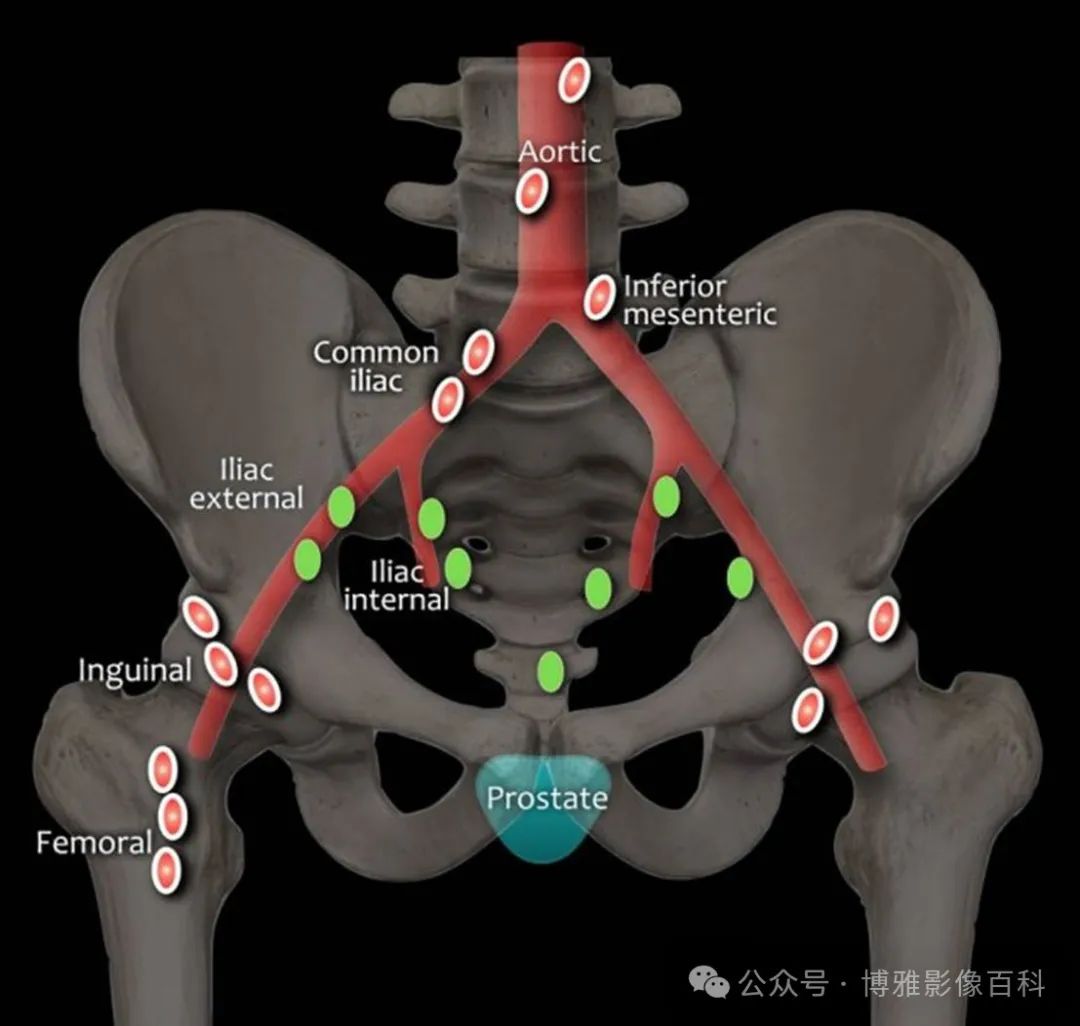

区域淋巴结

区域淋巴结(绿色)低于髂总交界处水平,分为 N1 分期:

远处淋巴结(红色)位于这些区域之外,分期为转移性疾病M1a: